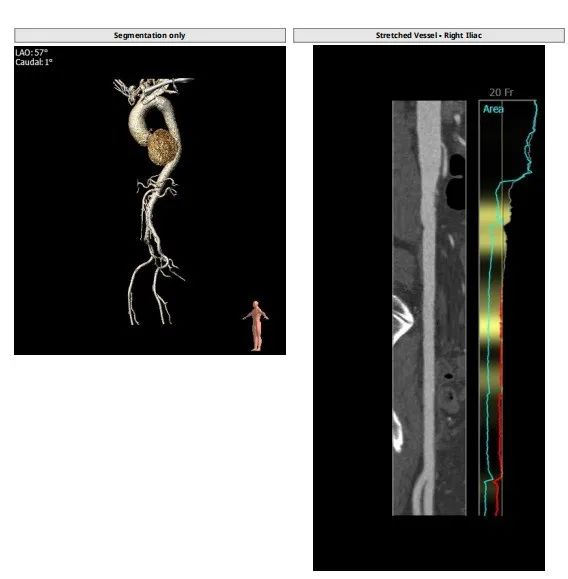

此例病人Type1二叶瓣,左右冠瓣融合,右无疑似融合,重度钙化,瓣环30.5,LVOT33.9,左右冠高度为16.9mm与18.8mm,右无融合离对侧28-30左右,STJ43.7,升主47.9,整体结构极大,心脏角度65度,近乎横位。